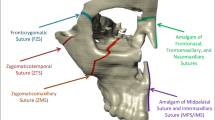

The geometric information of a human skull was imported into visual mesh software (version 7.0; ESI Group, Paris, France) to create a tetrahedral finite element (FE) mesh. The model included the maxilla, zygomatic bone, nasal bone, alveolar bone, teeth, and periodontal ligament. The skull model was generated using CT data from an adult male cadaver. To simulate the tissue and bone-borne palatal expander used in clinical practice, a virtual expander was created. It consisted of six miniscrews with a diameter of 1.6 mm and a length of 8.0 mm. The choice of 8.0 mm in length considered the thickness of the palatal mucosa. Bicortical positioning was not necessary as the miniscrews were placed on the palatal slope. The mesh size for the FE model was set at 2.0 mm, except for the area around the miniscrew, which was set at 0.2 mm to capture finer details (Fig. 4). The bone, teeth, and periodontal ligament structures were considered homogenous and isotropic. To replicate the opening pattern of the suture, the midpalatal and nasofrontal sutures were programmed to exhibit elastoplastic behavior. The modulus of elasticity and Poisson's ratio for each structure are provided in Table 3.

Sutures were modeled to exhibit elastic bilinear behavior based on a previous study. The initial Young's modulus for the sutures was set to 1.0 MPa. A threshold stress (transition) of 0.1 MPa was defined, indicating the point at which the material transitions from elastic to plastic behavior. The final elastic modulus was set at 0.01 MPa, representing the stiffness of the material after the transition.32 To establish a fixed reference point, the foramen magnum was set as immobile and served as the origin point in the coordinate system. The coordinates within the model were defined using the transverse plane as the X axis, the sagittal plane as the Y axis, and the vertical plane as the Z axis. This coordinate system allowed for the precise analysis and measurement of displacement and stress distribution within the model.

Ten experimental models were created, each with different placement positions for the miniscrews. In Model A, the miniscrews were placed between the roots of the first and second premolars, between the roots of the second premolar and first molar, and between the roots of the first and second molars, all positioned at a point 7 mm below the cemento-enamel junction (CEJ). Model B had the same miniscrew locations as Model A, except they were placed at a point 15 mm below the CEJ. For Models C, D, E, and F, three miniscrews were selectively placed between the first and second premolars and between the second premolar and first molar, at both 7 mm and 15 mm below the CEJ. Similarly, for Models G, H, I, and J, three miniscrews were selectively placed between the second premolar and first molar and between the first and second premolars, also at both 7 mm and 15 mm below the CEJ (Fig. 5). The specific distances of 7 mm and 15 mm below the CEJ were determined based on a previous study for consistent and standardized placement across the models.23.

To observe detailed changes in the nasomaxillary complex and nasofrontal suture, five specific landmarks were included in the analysis. These landmarks, as depicted in Fig. 6, are as follows:

Z: The most lateral point of the zygomatic arch in the frontal view.

N: The most lateral point of the piriform aperture on the maxillary bone surface.

ANT: A 2 mm lateral point from the midpalatal suture on the line connecting the bilateral upper canines.

TPS-M: A 2 mm lateral point from the midpalatal suture on the transverse palatal suture.

TPS-L: The most lateral point of the transverse part on the transverse palatal suture.

These landmarks were selected to capture specific locations and provide a comprehensive evaluation of the changes in the anterior and posterior parts of the palate and the nasomaxillary complex. The ratios of ANT to TPS-M and ANT to TPS-L were calculated to compare the expansion patterns between the anterior and posterior parts of the palate, respectively.